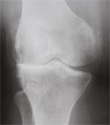

X-ray of normal knee and knee with arthritis. Notice the loss of joint space with bone touching bone in the knee with arthritis.

X-ray of Knee With Arthritis